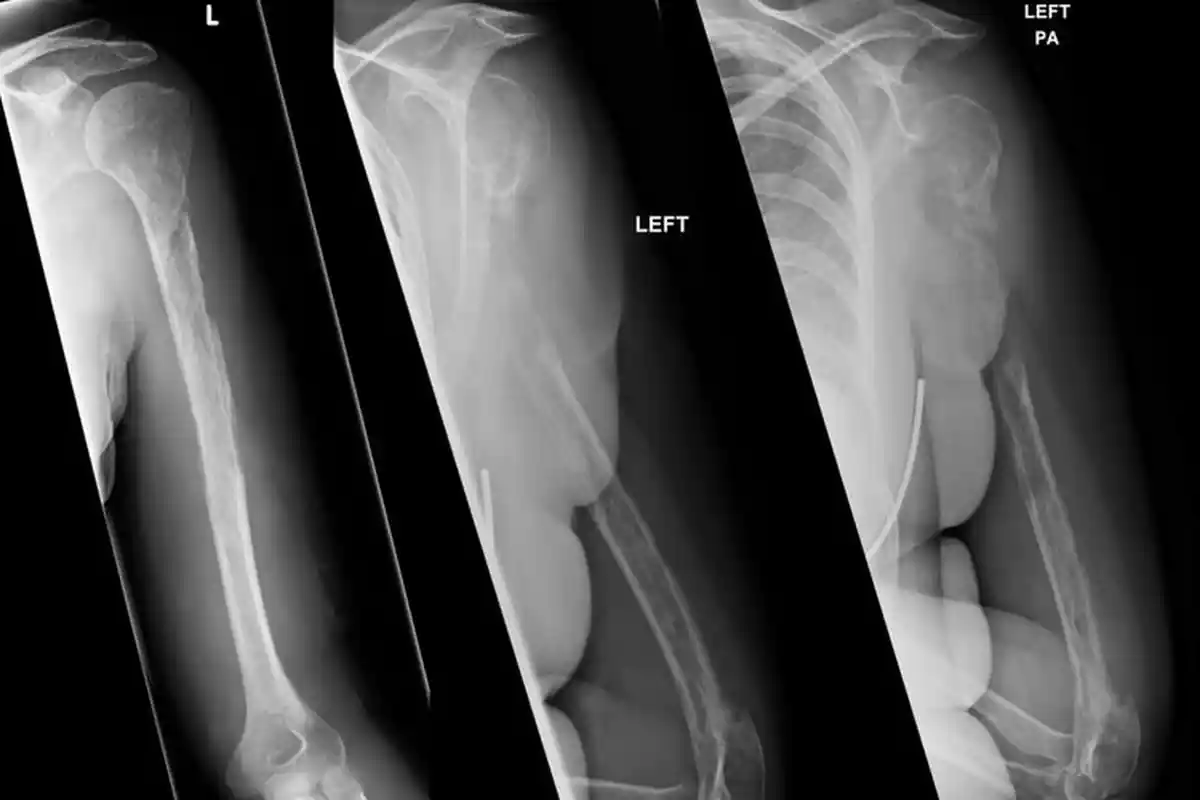

TRIBUNMANADO.CO.ID -Sebuah penelitian yang dipublikasikan di Journal of Bone and Mineral Research Para peneliti mengamati apa yang terjadi pada lemak sumsum tulang dan kesehatan tulang secara keseluruhan ketika terjadi pembatasan asupan kalori.

Penelitian lainnya yang dilakukan pada 2019 mengungkapkan, diet dengan mengonsumsi kalori hanya 30 persen, setara dengan 1.400 kalori per hari untuk lalu dikombinasikan dengan olahraga, dapat menyebabkan hilangnya kepadatan tulang.

Peningkatan lemak pada tulang bagi mamalia, termasuk manusia, dianggap berbahaya karena membuat tulang menjadi lebih lemah.

Lemak yang lebih sedikit pada tulang biasa dianggap sebagai indikasi kesehatan tulang yang lebih baik.

Dari persepektif manusia, diet rendah kalori meski bernutrisi baik dapat memiliki efek negatif pada kesehatan tulang, terutama ketika dipasangkan dengan olahraga.